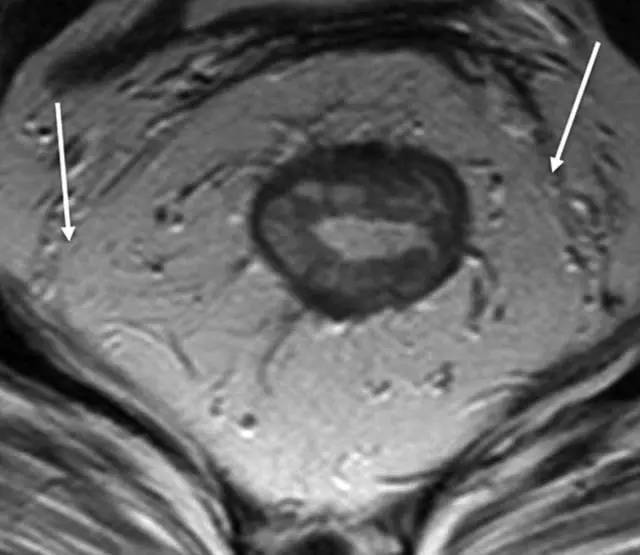

图片

箭头显示直肠系膜筋膜。